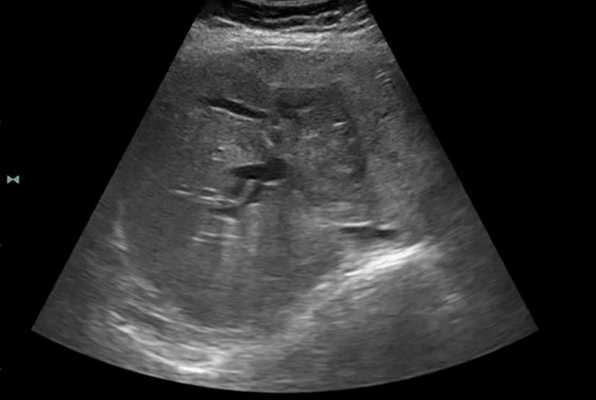

Маркеры инфицирования вирусами гепатитов В и С не обнаружены. По данным УЗИ органов брюшной полости (май 2016 г.): печень расположенатипично, правая доля толщиной 125 мм, левая доля толщиной 50 мм, структура паренхимыдиффузно неоднородная, зернистая, смазанная, с эффектом акустического затухания, гиперэхогенная, сосудистый рисуноксмазан, обеднен на периферии; воротная вена в воротах печенине расширена, проходима (11 мм); печеночные вены не расширены. В V6—7 сегментах выявлены гипоэхогенные образования округлой формы размерами 45×29 мм, 32×23 мм, 31×22 мм, по ходу гастродуоденальной связки и в проекции головки поджелудочной железы округлые гипоэхогенные образования размерами 32×26 мм, 20×18 мм, 20×10 мм (измененные лимфоузлы?). Желчный пузырь, желчные протоки, поджелудочная железа, селезенка не изменены. Свободная жидкость в брюшной полости не определяется. Заключение: признаки очаговых образований печени и измененных лимфоузлов брюшной полости, диффузных изменений печени по типу жировой дистрофии, диффузных изменений поджелудочной железы.